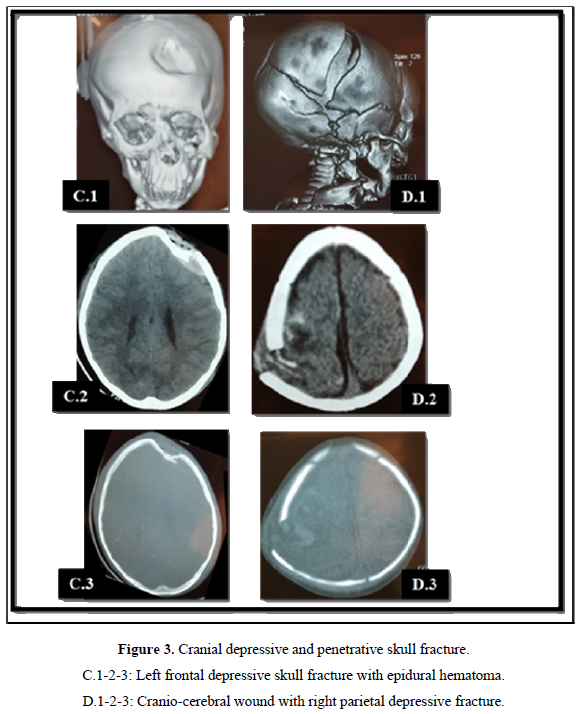

Computed tomography (CT) was the exam of choice for diagnosing lesions. It was performed in all patients and had made it possible to highlight a depressed skull fracture in 45 patients (62.5% of the cases) (Figure 2). These depressed skull fractures were isolated in 7 patients (15.6% of cases). They were associated with brain contusions in 36 cases (80%) Figure 2A and acute subdural hematoma in 2 patients (4.4%) Figure 2B. Isolated brain contusion was diagnosed in 18 patients (25%). Extradural hematoma (Figure 3C) and craniocerebral wound (Figure 3C) each accounted for 2.7% (2 cases). In 5 patients (7%), the CT scan was normal.